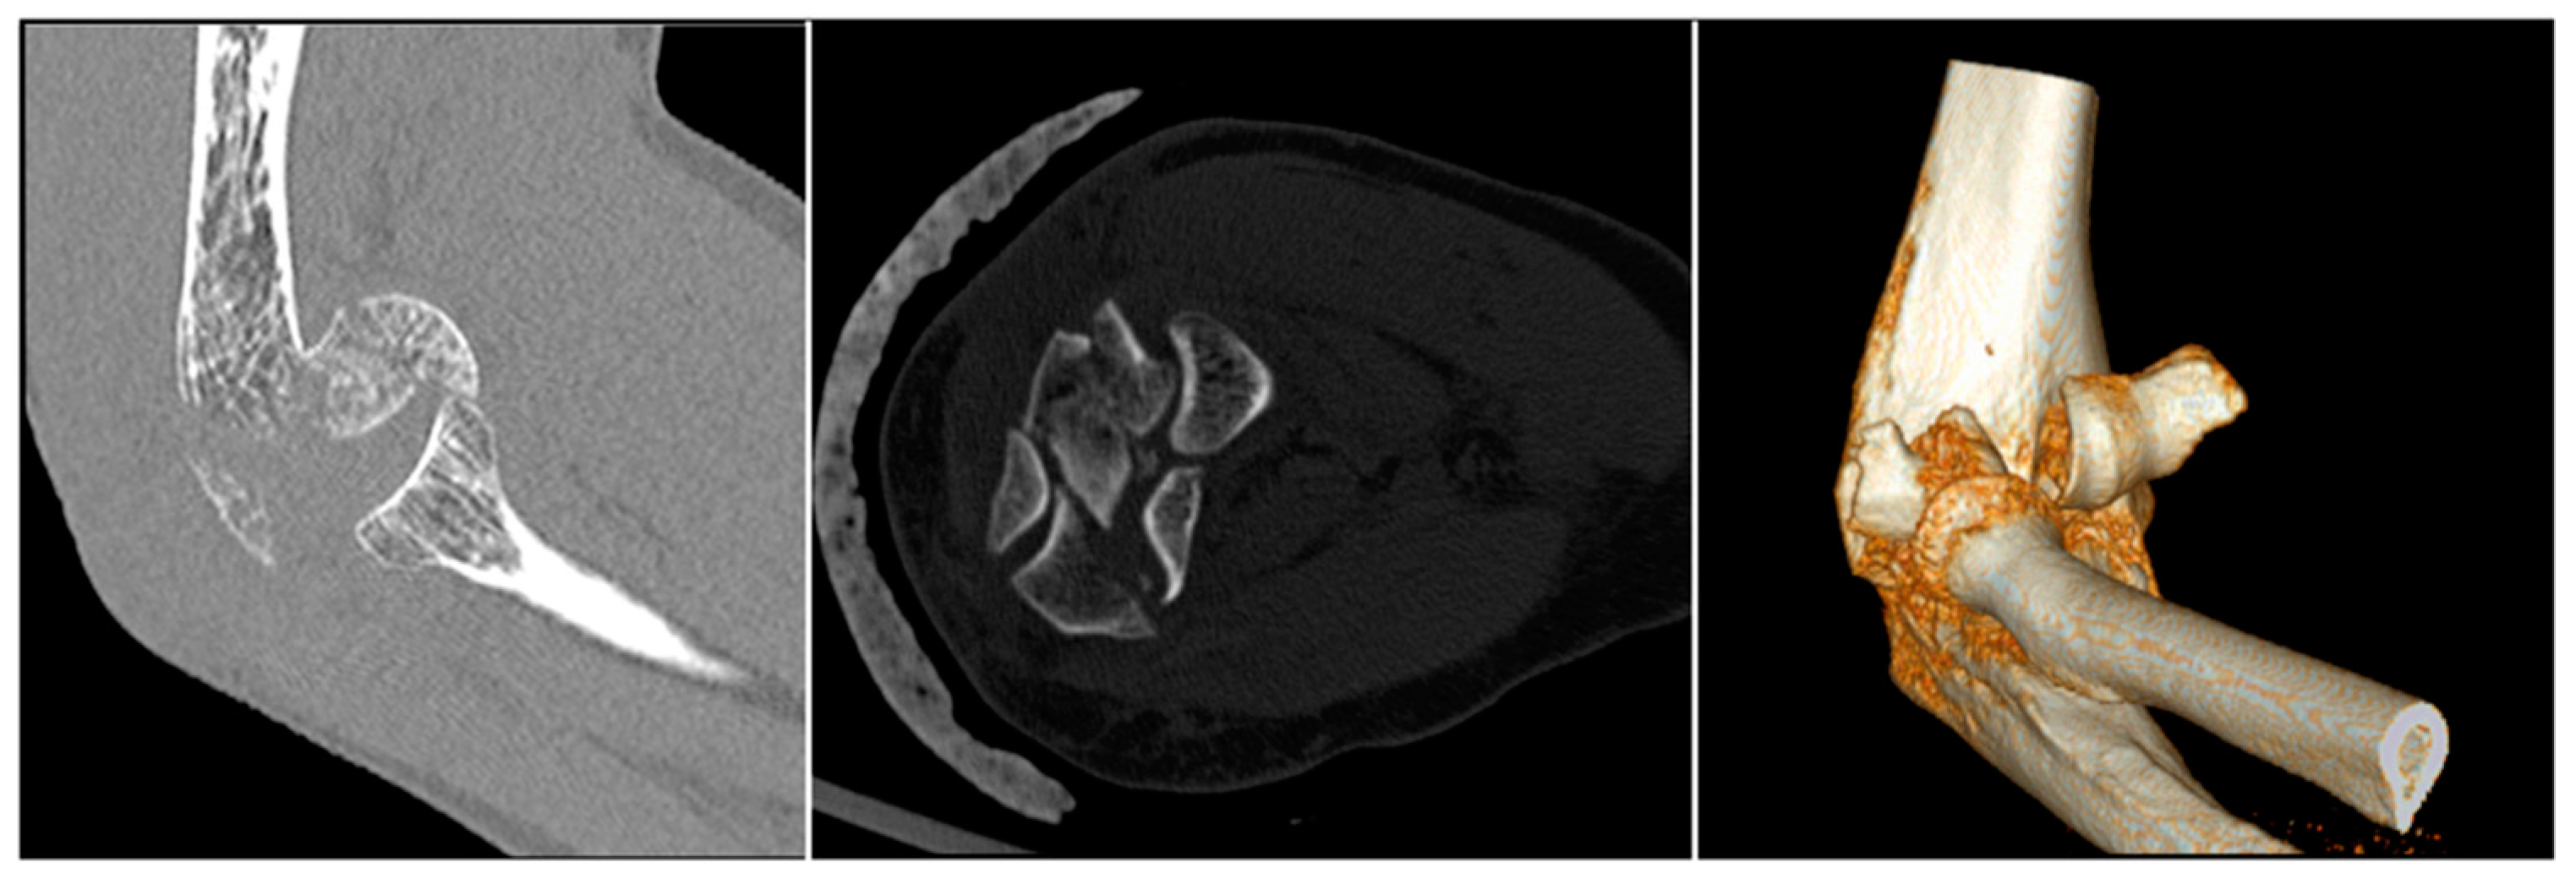

3. Imaging